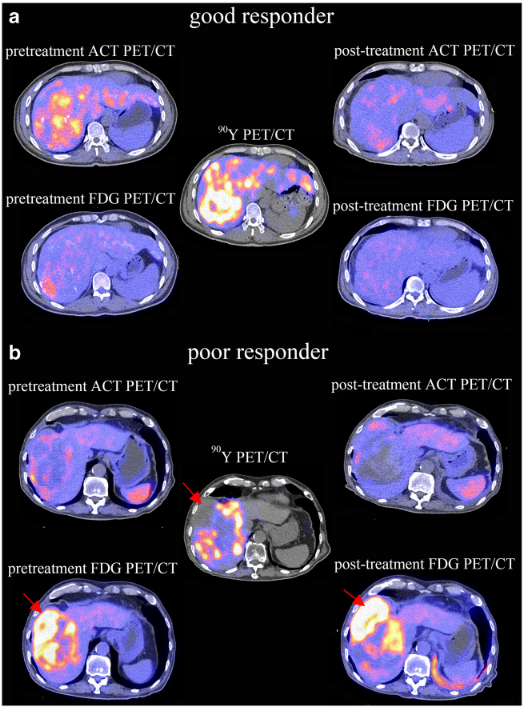

11C标记醋酸和18F标记葡萄糖与90钇肝肿瘤体内放射治疗的同步互动关系